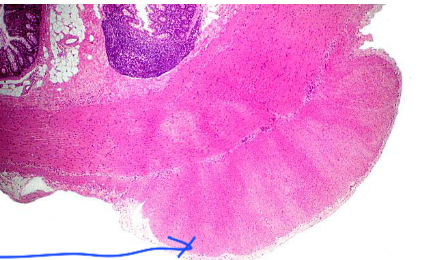

21

Q

wheres this from

whats the arrow pointing to

A

large intestine

tenia coli

How well did you know this?